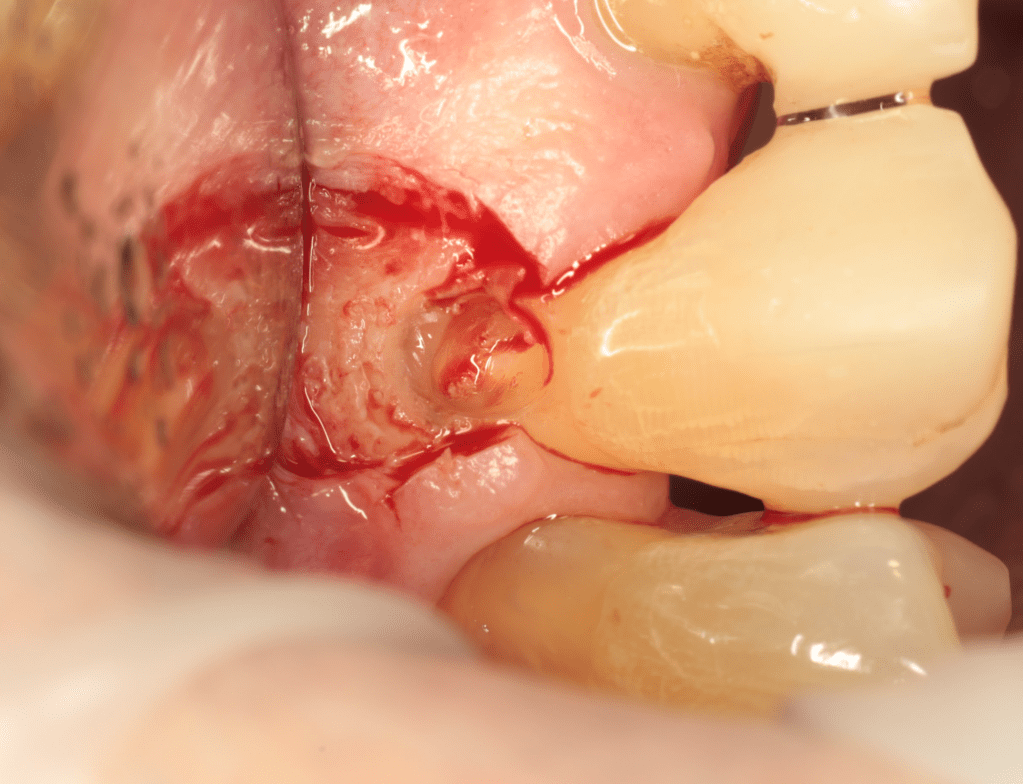

Reabsorción externa, tratamiento quirúrgico

Extrusión quirúrgica

Gingivectomía +reco preendo +reconstrucción

Reco pre-endo gingivectomái, pared yuxtaosea